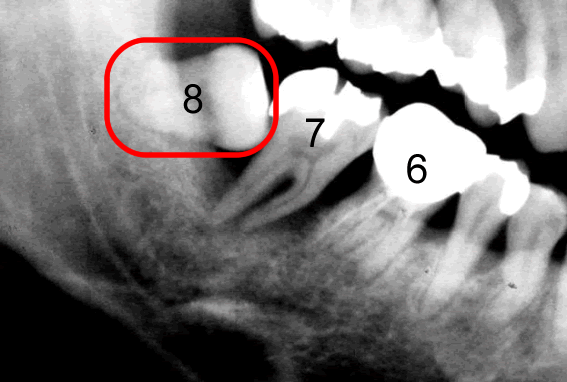

右下部分を切り出して拡大しました。

8と赤く囲んでいる部分が親知らずです。横に向いて生えていますね。親知らずの手前の歯7番目、その手前の歯6番目、どうなっているでしょう?6番目は全体写真で鼻の骨を起点にみると斜めに倒れて、かつ、上に上がっていますね。親知らずに押し上げられているんですね。神経の治療も受けられて何度も治療されています。

このレントゲン写真でもう一つ重要なことが、あります。それは、親知らずのすぐ手前の7番目の歯の根っこをご覧下さい。根の周囲が黒いですよね。歯を支えている骨が溶けているんです。

レントゲン写真というのは硬いところが白くうつります。5番目の歯の根っこのあたりは歯の根の周りがまだもや~っと白くうつっています。これは硬い「骨」が写っているんです。しかし、7番目には、骨が、ない。

さらに6番目の根っこの7番目よりのあたりまで骨が溶けています。7番目の歯を支えている骨が全然ないのです。6番目の歯を支えている骨が後ろ半分すでにないのです。ということはこの7番目の歯はグラグラに揺れています。抜かなければならないということです。ほっといてもそのうち7番目は勝手に抜けます。ほっておくと6番目も同じ運命になります。「親知らず」を抜かずに放置しておいたために、その「親知らず」が横に押し上に押し、さらにこの7番と8番の間に溜まったバイ菌が取りきれないわけです。ここはどんなにご自身で歯ブラシをしても、フロスをしてもばい菌を取りきること は出来ません。歯周病とは「歯を支えている骨が溶ける病気」です。つまりこの方は親知らずが原因で「歯周病」を引き起こしてしまっているということなのです。